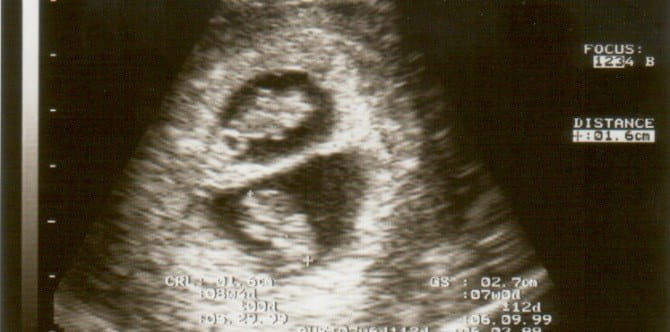

In 2006, Kate Hill was diagnosed with polycystic ovarian syndrome (PCOS), a hormonal condition that prevented her from ovulating, BBC reports. After hormone treatments, Kate and her husband Peter were delighted to find out that she was pregnant. 10 days later, they found out that she had conceived again!

Kate initially conceived twins, but one baby didn’t develop. Almost two weeks later, while pregnant, she became pregnant again. Even though Kate was pregnant, she had ovulated again, causing her to become pregnant one more time.

This phenomenon is called superfetation. Superfetation occurs when an already-pregnant woman ovulates weeks into her pregnancy. The second egg gets fertilised, causing the pregnant to be pregnant with twins.

Superfetation is very rare because it isn’t supposed to happen. “Pregnancy hormones usually shut down a woman’s system, making it impossible for her to ovulate during her pregnancy,” obstetrician Connie Hedmark explains to BabyCenter. “This is why superfetation is so remarkable.” (This is totally different from superfecundation, which is when two eggs are released simultaneously and fertilized at separate times.)

According to Pregnancy Corner, only around 10 cases of superfetation have been documented in medical literature, and experts are suspicious even of some of these. But many experts also say that superfetation may be more common than we think, as some cases may be mistaken for ordinary twin pregnancies.